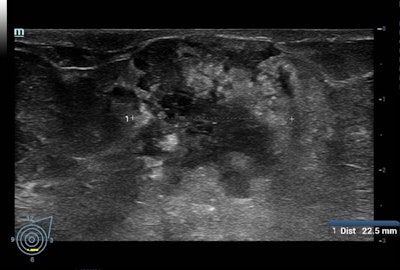

La force du programme national de dépistage réside dans le fait qu'il est décentralisé, ce qui signifie qu'il peut avoir lieu près du domicile des patients - dans l'un des 2 700 centres de mammographie en France - et peut être adapté au patient, selon Ceugnart, qui est chef du département d'imagerie, au Centre Régional de Lutte Contre le Cancer Oscar Lambret de Lille. L'échographie est systématiquement proposée aux patientes aux seins denses et elle est réalisée lors de la même consultation de dépistage par un radiologue, plutôt que lors d'un rendez-vous de suivi.

Par exemple, l'étude ASTOUND (dépistage adjuvant avec tomosynthèse ou échographie chez les femmes ayant des seins denses et avec une mammographie négative) a montré que l'échographie permet une meilleure détection du cancer du sein que la DBT dans les sein denses avec une mammographie normale avec un taux de rappel similaire. Cependant, selon les auteurs, la DBT a détecté plus de 50% des cancers du sein supplémentaires chez ces femmes.

En outre, l'étude J-START (Essai randomisé stratégique contre le cancer au Japon) a révélé que l'échographie d'appoint augmentait la sensibilité et le taux de détection des cancers à un stade précoce.